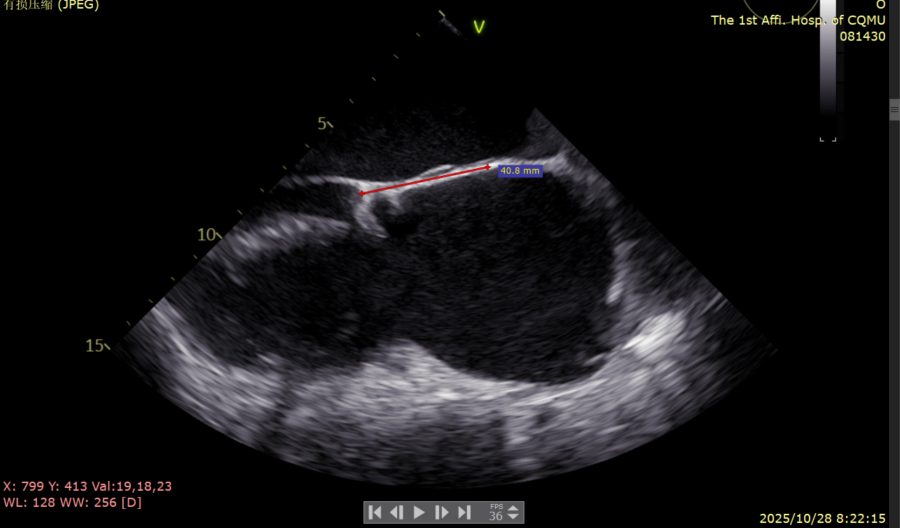

三尖瓣术前评估

术前食道超声评估:三尖瓣重度反流,FTR6+,反流位于前隔、中央,后隔。瓣叶粘液样变性,后隔可见4.6mm gap。

图1、图2:2区瓣叶长度(前叶长度2.46cm,后叶长度1.15cm)及彩色血流